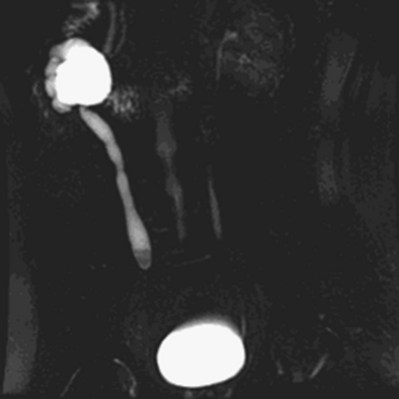

Compensatory renal growth (CRG) of the unobstructed kidney was first described by Hinman (1943). This phenomenon has been subsequently demonstrated in a number of other animal models of UUO (Taki et al, 1983; Peters et al, 1993). There is evidence that it occurs in the human fetus. An increase in contralateral renal volume has been detected ultrasonographically when contralateral hydronephrosis or unilateral renal agenesis is present (Mandell et al, 1993).

The mechanisms and nature of this growth are influenced by several factors including age, and degree and duration of obstruction. Both hyperplastic and hypertrophic CRG have been demonstrated (Dicker and Shirley, 1973; Castle and McDougal, 1984; Peters et al, 1993). CRG was demonstrated to decrease progressively with increasing age at which the obstruction occurred in animal models (Taki et al, 1983). Studies of humans subjected to nephrectomy, a functional surrogate for obstruction, have demonstrated that a reduction in CRG occurs with increasing age (Edgren et al, 1976). Animal experiments have also demonstrated that compensatory growth is directly proportional to the duration of obstruction (Chevalier et al, 1999). Compensatory growth is less prominent with partial than with total UUO (Chevalier and Kaiser, 1984; Eskild-Jensen et al, 2001). While the kidney enlarges, an increase in the number of nephrons or glomeruli does not occur (Peters et al, 1993). However, an increase in the length of the proximal tubule has been described, which may be due to an increase in cell size (Moller, 1988). In addition, there is augmented extracellular matrix synthesis and growth of mesangial cells (Kasinath et al, 2006; Sinuani et al, 2006). Insulin-like growth factor I (IGF-I), a mitogenic and anabolic peptide, may play a role in compensatory renal growth after obstruction. There is both animal and clinical evidence for its role. In rats, mean renal IGF-I is significantly elevated in the normal kidney compared with the contralateral 7-day obstructed kidney (Serel et al, 2000). Inferences can also be made from nephrectomy performed in animals and humans. Renal IGF-I mRNA levels are increased in immature rats previously subjected to nephrectomy (Mulroney et al, 1991). Significant increases in serum IGF-I have been demonstrated in humans after donor nephrectomy and peak 6 months after the procedure. Serum IGF-I was positively correlated with increases in renal volume demonstrated on serial postoperative imaging (Nam and Chang, 1999). It has also been demonstrated that the expression of IGF-I may be age dependent. Although renal IGF-I mRNA levels were found to be elevated after nephrectomy in immature rats, this did not occur in adult rats (Mulroney et al, 1991). Exogenous IGF-1 can attenuate renal injury from obstruction (Chevalier et al, 2000). Other growth factors, cytokines, and enzymes may be involved in regulating CRG, including IGF binding protein–3 (IGFBP-3), vascular endothelial growth factor (VEGF), matrix metalloproteinase–9 (MMP-9), interleukin-10 (IL-10), and TGF-β (Yildiz et al, 2008). Experimental studies suggest that CRG may be influenced by mitochondrial respiration (Tucci et al, 2008). The presence of compensatory growth in infants has been considered by some as an indicator that contralateral hydronephrosis is functionally significant (Koff and Peller, 1995). However, this approach has been challenged by others (Brandel et al, 1996). In addition, it was demonstrated that functional deterioration occurred in a rat model of partial UUO before compensatory growth developed in the contralateral renal unit. This implies that there may be a risk for functional renal loss if one uses only compensatory growth as an indication of correction of obstruction (Wen et al, 1999). Studies in children with unilateral renal tumors have shown that partial nephrectomy is associated with a greater degree of CRG versus nephrectomy, as assessed by ultrasonography (US) (Cozzi et al, 2007). The cause for this differential response is unknown but may be due the generation of more CRG factors in this setting.